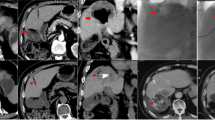

To evaluate the relationships among VLs, additional GS embolization, and local response, the 338 nodules were retrospectively divided into three groups according to the onset of VLs and the need for additional GS embolization to deal with non-shrinking VLs: lesions without a VL (non-VL group, n = 250); lesions with a VL but without an additional GS embolization [VL–GS (−) group, n = 58] (Fig. 1); and lesions with both VL and additional GS embolization following DEB injection [VL–GS (+) group, n = 30] (Fig. 2).

A lesion with a vascular lake (VL) that was not additionally injected with gelatin sponge particles (GS) in the VL–GS (−) group. The patient was a 68-year-old female with multiple recurrent hepatocellular carcinomas (HCCs) after repeated conventional transcatheter arterial chemoembolization. a Contrast-enhanced computed tomography (CECT) showed a 2.0-cm HCC at a peripheral site in the hepatic anterior segment (arrow). b Selective angiography of the anterior segmental branch of the right hepatic artery showed two tumor blushes, one of which was identified as a contrast-enhanced lesion in liver segment 5 on CECT (arrow). Chemoembolization was performed at this point. c Selective angiogram after chemoembolization with 7 mg of drug-eluting beads (DEBs) showed VL formation (arrow) with complete disappearance of the tumor blush. d CT during selective angiography just after chemoembolization showed pooling of the contrast material within the tumor (arrow), representing VL formation. e Selective angiography showed disappearance of the VL after additional injection of 1.0 mg of DEBs alone. f CECT at week 4 after chemoembolization revealed a lack of contrast enhancement in the majority of the tumor areas (arrow), suggesting a partial response